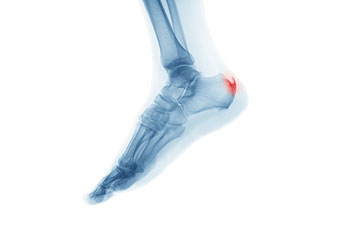

Heel spurs are brought upon by a calcium deposit that causes a bony protrusion on the underside of the heel bone. It normally forms over time and can best be diagnosed through an x-ray examination. Heel spurs are commonly linked with plantar fasciitis, an inflammation that runs along the bottom of the foot. Common symptoms of heel spurs include pain towards the affected area, inflammation, and swelling at the front of the heel.